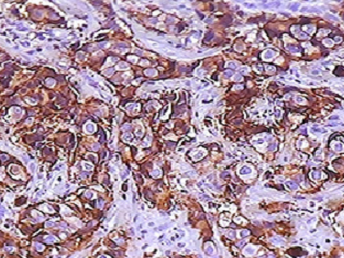

Patología de Mama

Analizamos cualquier tipo de muestra de mama, incluyendo especímenes extraídos de patología quirúrgica, las biopsias y aspiraciones de aguja fina.

El laboratorio de inmuno-histoquímica proporciona el análisis de expresión de Receptores hormonales, Her2 neu, índice de proliferación y otros marcadores.